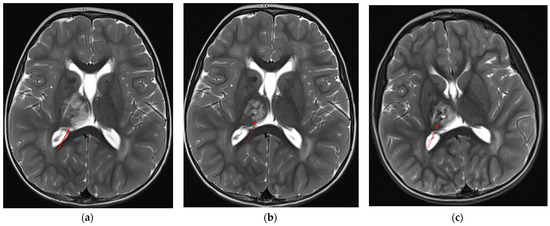

To assess the evolution of the neuroradiological picture and to decide whether to propose an off-label therapy with bevacizumab, the child underwent neuroradiological follow-up at 6-month intervals through brain MRI, which documented spontaneous dimensional reduction of the known signal alteration at the right mesial thalamic site and stability of the leukoencephalopathy (Figure 3a–c).

Figure 3. Axial T2-TSE showing progressive reduction and cystic degeneration of the right thalamic lesion (red arrows): (a) 2 years and 4 months of age, (b) almost 3 years, (c) last MRI at almost 5 years of age.